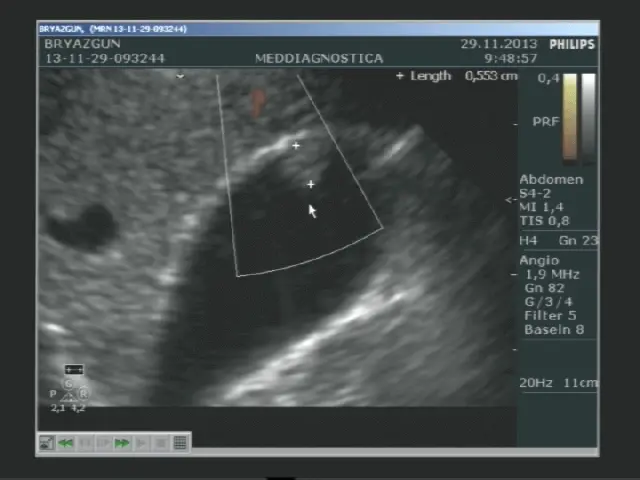

Лікар наносить на область живота спеціальний гель, після цього водить по шкірі ультразвуковим датчиком. На моніторі вимальовується картинка області дослідження. Лікар робить помітки, заміряє розміри і щільність органів, вивчає клінічну картину.

Дослідження проводиться на сучасній апаратурі з використанням передових технологій, що мінімізують похибки вимірювань. Доктора, які проводять дослідження мають відповідну кваліфікацію.